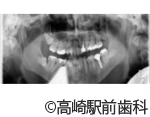

【症例3】上の歯すべて連続のインプラントでのブリッジ(ガイドを使ったオールオン8)

- 治療前

- 治療後

- 治療名

- 上の歯すべて連続のインプラントでのブリッジ(ガイドを使ったオールオン8)

- 費用

- 2,280,000円(税込10%)

- 期間

- 2ヵ月半

治療内容

患者様の症状

・上の歯のブリッジが壊れて全部とれたので噛めない(すぐに仮歯が必要)

・残っている歯がもう使える状態ではない(すべて抜歯が必要)

・見た目をきれいに治療したい

・入れ歯にはしたくない -

治療法

8本インプラント埋入してインプラントブリッジ

・右上のインプラントする部位に骨がないので人口骨にて増骨する

・見た目が綺麗なまま劣化しない、ジルコニアで作るダイアモンドセラミックのブリッジで完成

・痛みを抑えた、腫れない治療を希望にて、ガイドを使ったメスを使わないインプラント手術(そのため切らない、縫わないインプラントが可能) -

治療結果

上顎部分全体にきれいな、噛める状態に改善することができました。

※治療結果は患者様によって個人差があります。